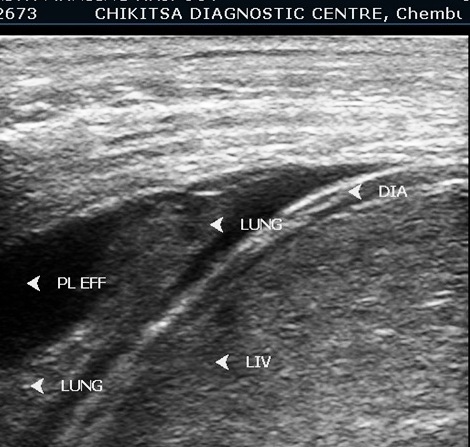

A chest ultrasound may used to assess the presence of excess fluid in the pleural space or other areas of the chest.

Chest ultrasound may be performed to guide a needle to puncture the chest wall for the removal of fluids.